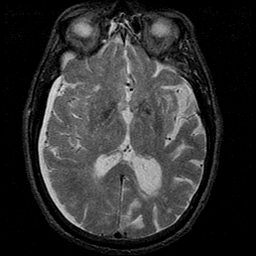

Subdural Hygroma,overlay -- Slice #24